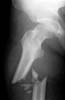

Λονδίνο: Τα άτομα που υποβάλλονται σε χειρουργικές επεμβάσεις αντιμετώπισης της παχυσαρκίας διπλασιάζουν τον ατομικό τους κίνδυνο να υποστούν οστικά κατάγματα, σύμφωνα με αμερικανική μελέτη που παρουσιάστηκε στο ετήσιο συνέδριο της Αμερικανικής Εταιρείας Ενδοκρινολογίας.